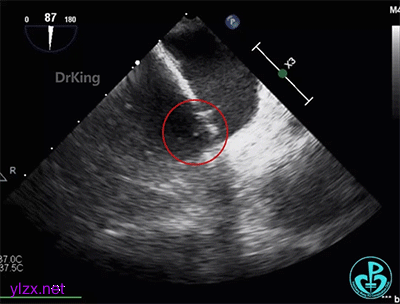

术前经食道超声描述:室间隔连续完整,房间隔中部菲薄,呈瘤样凸向右房面,基底宽约12mm,膨出约8mm。卵圆窝处薄弱,呈纤细线样回声,原发隔与继发隔间见纤细裂隙,入口约0.4mm,出口约0.8mm,卵圆瓣长约20.1mm,原发隔摆动幅度约13mm,继发隔厚约4.5mm,瓦式呼吸后,入口较宽约3.8mm,出口较宽约2.0mm,卵圆瓣左房侧末端迂曲。CDFI裂隙处可见微量左向右过隔血流信号。左心耳显示清楚,内未见异常回声。主动脉内中膜欠光滑,窦部宽约25mm,管腔未见明显狭窄与扩张,CDFI未见明显异常血流信号。各房室腔比例尚可,未见明显节段性室壁运动异常,各瓣膜形态、结构正常,启闭尚可。

超声诊断:先天性心脏病,卵圆孔未闭(长隧道型)。

右心声学造影检查:微泡造影剂经右肘正中静脉、上腔静脉进入右房,充盈良好,可见小楔形负性充盈区,患者瓦氏呼吸后见细小微气泡自裂隙处进入左房,约25~30个,一个裂隙位于卵圆孔入口处,一个位于卵圆孔出口处。

经食道超声三维、二维和右心声学造影图像: